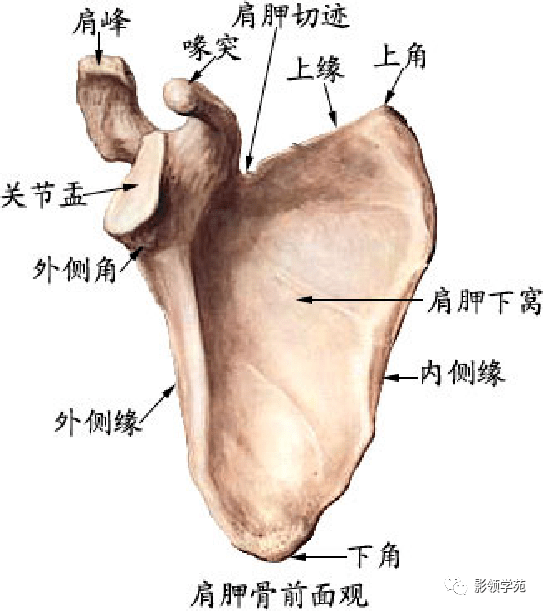

骨骼系统

骨骼系统